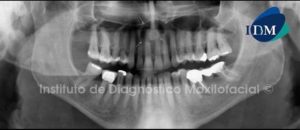

Paciente de sexo masculino de 54 años de edad, el cual manifiesta no presentar síntomas y es referido para la respectiva evaluación radiográfica previo al tratamiento con implantes.